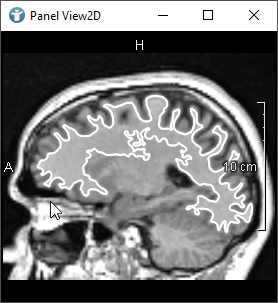

As mentioned, when creating CSOs, you can do this interactively by using an editor.

The following images show editors available in MeVisLab for drawing CSOs:

The SoCSOIsoEditor and SoCSOLiveWireEditor are special, because they are using an algorithm to detect edges themselves.

- The

SoCSOIsoEditorgenerates isocontours interactively. - The

SoCSOLiveWireEditorrenders and semi-interactively generates CSOs based on the LiveWire algorithm.